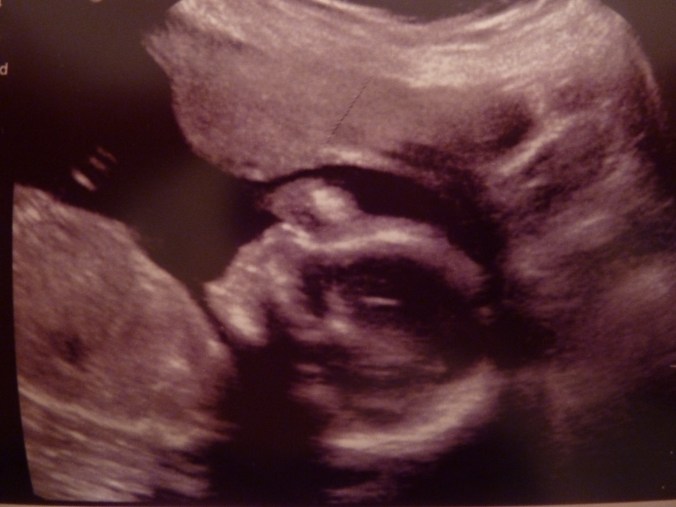

So, I had my big 20-week sonogram this afternoon and…

P1160894

The best news of all is that baby #3 looks perfectly healthy. (And judging from all the jumps I’m feeling, also quite happy!)

P1160893

Just like my first two, this one didn’t cooperate too well with the test. It took three goes for the technician to get all the information she needed.

P1160892

However… baby wasn’t at all shy about revealing gender.